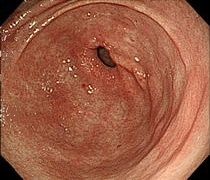

胃がんの精査は主に上部消化管X線検査(胃透視)と上部消化管内視鏡検査(胃カメラ)があります。当院では早期発見により有効な検査である内視鏡検査(胃カメラ)を主に行っています。 がんを疑う病変に対しては、内視鏡で観察しながら鉗子(かんし)と呼ばれる器具で病変の一部を採取(生検)して、顕微鏡による病理診断を行い、がんの有無を調べます。

早期胃がん

(NBI画像)